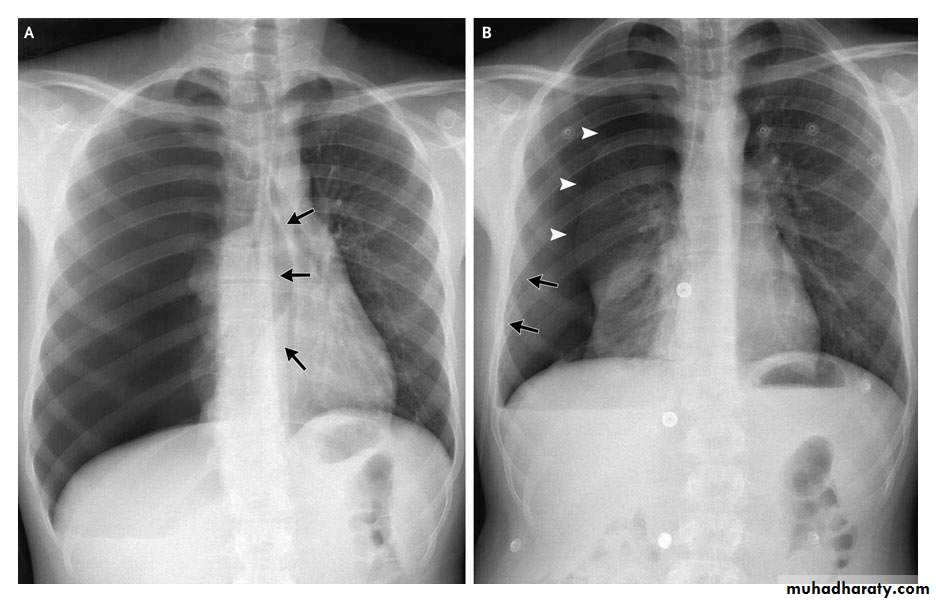

What is the difference??

Massive effusion

Whole lung atelectasisEmpyema

CXR: